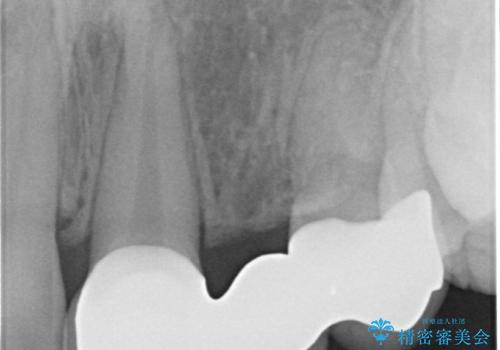

- 歯列矯正後に前歯にブリッジを入れた方の経過です。

矯正治療の術前後の経過は以下をご覧ください。

矯正治療で歯の位置を整えてからブリッジを入れると歯の幅を自由に設定できるため、左右対称にできます。結果矯正なしでいきなりセラミックにする場合と異なり、無理に角度を変えたりする必要がなく、神経をなるべく温存したまま審美的なセラミック治療が行えます。